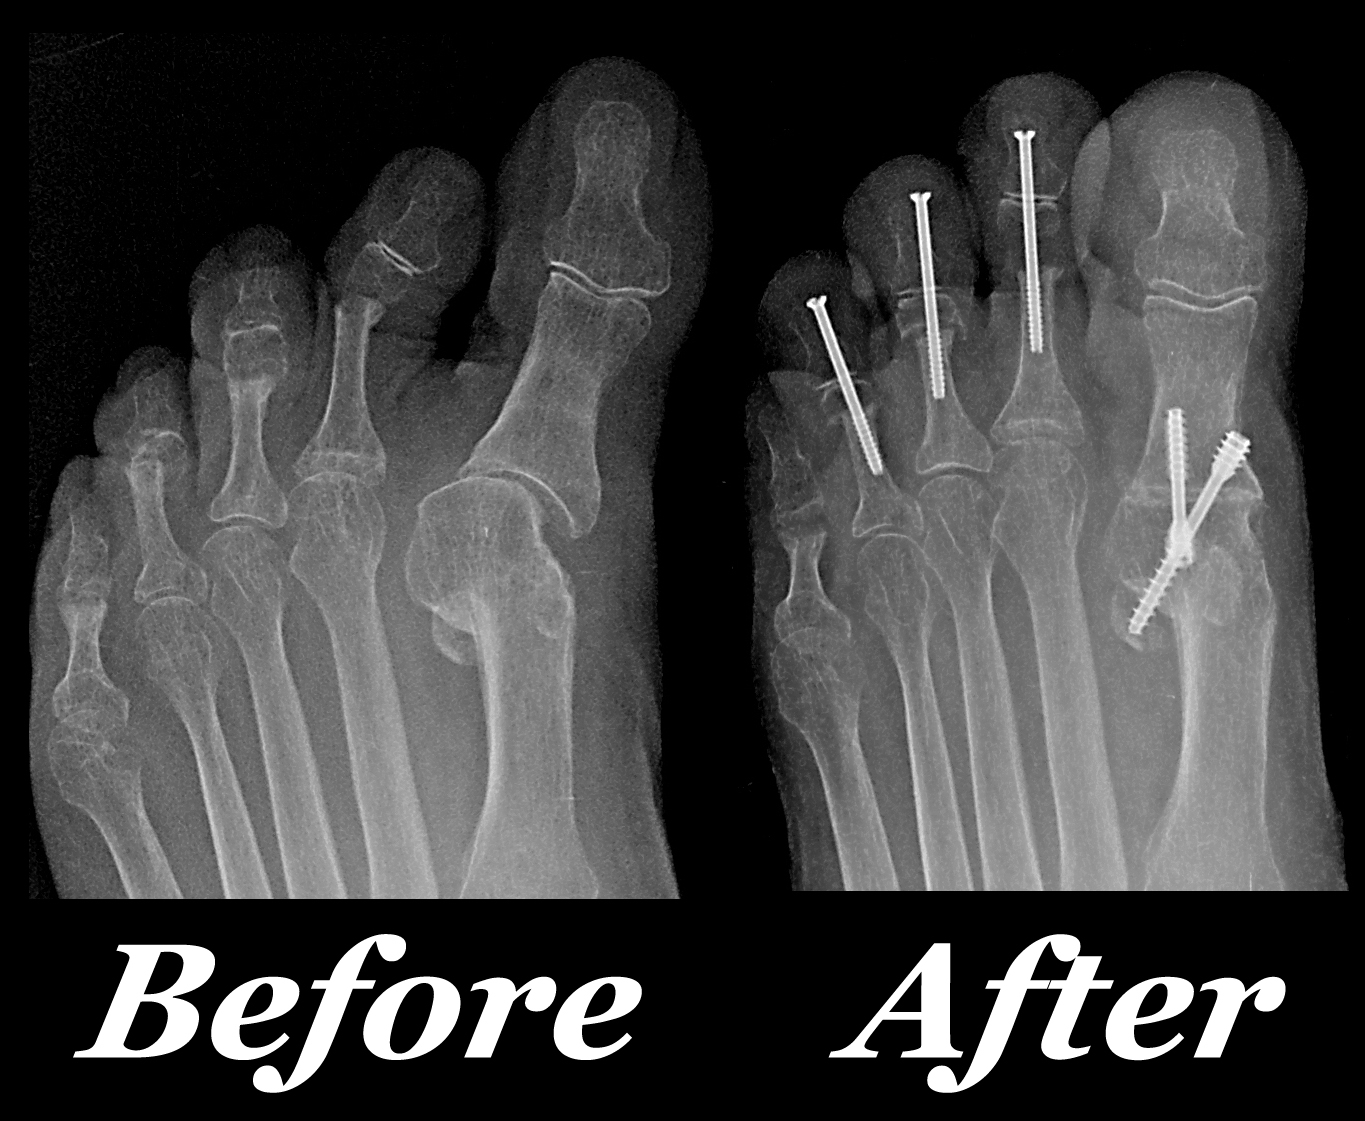

From foot-essential.blogspot.com

Foot Essential Blog Fused Bones Examples A ridge across the front or anterior portion of the. Nodes represent bones and links represent articulations among bones (cartilaginous and fibrous joints). A prominent example of a fixed joint is the skull, which is made up of a number of fused bones. The human skeleton is the internal framework of the body. The sacrum is an irregular bone that. Fused Bones Examples.